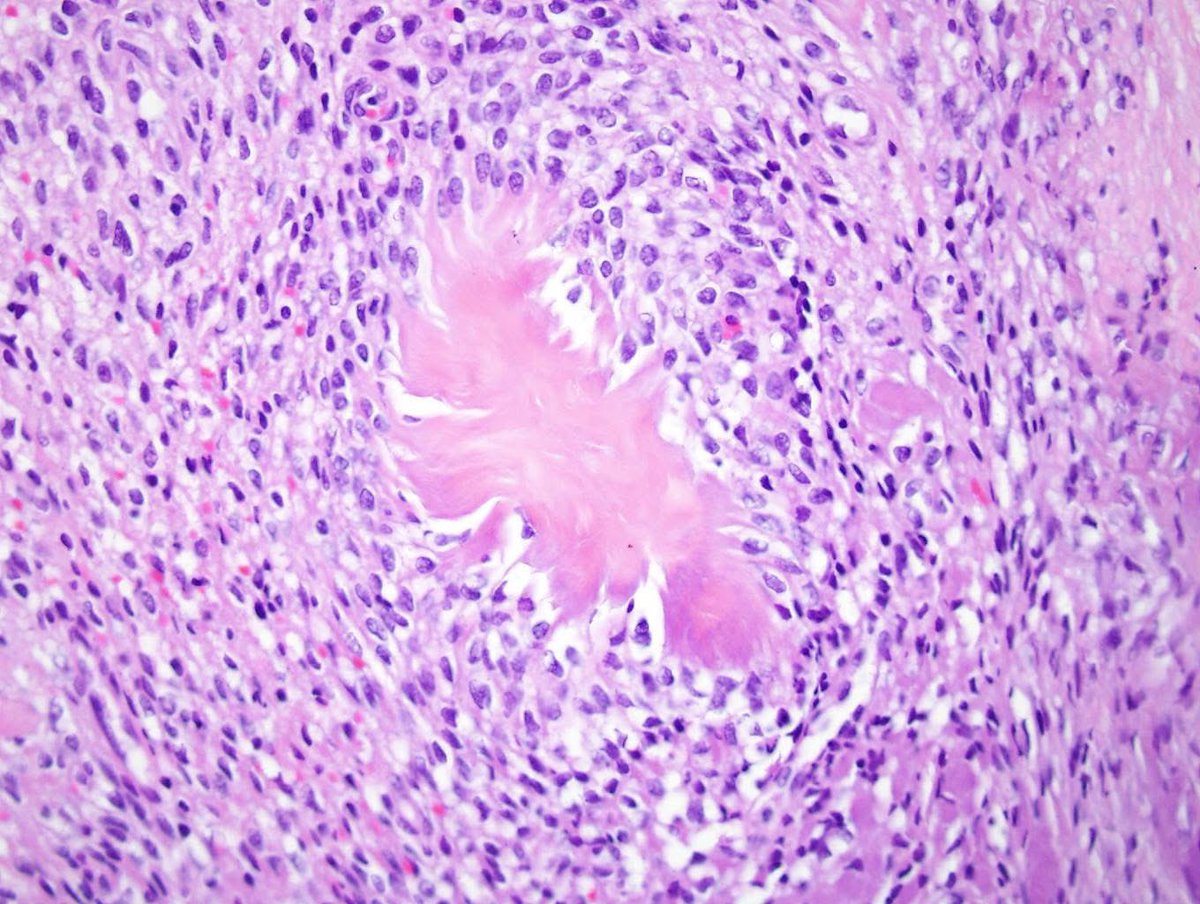

A rectal biopsy showing metastatic endometrial stromal sarcoma with 😎 💥 burst collagen and positive ER stain.Credits:ARP Press.@DrMarkOng

@smlungpathguy @pepeheffernan @SumantaDas_7 @MirunaPopescu13 @DanGrahamMD @Venkateshgilly2 @drtimbracey @GIJamesMD @kis_lorand